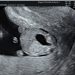

Guida al Counselling di Luglio 2024: corpo luteo emorragico

vi presentiamo la guida al counseling di Luglio 2024 sul corpo luteo emorragico.